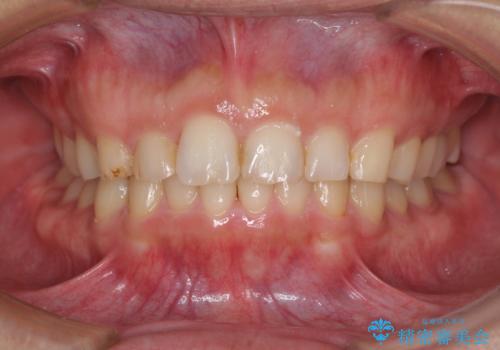

- 患者様

- 50代男性